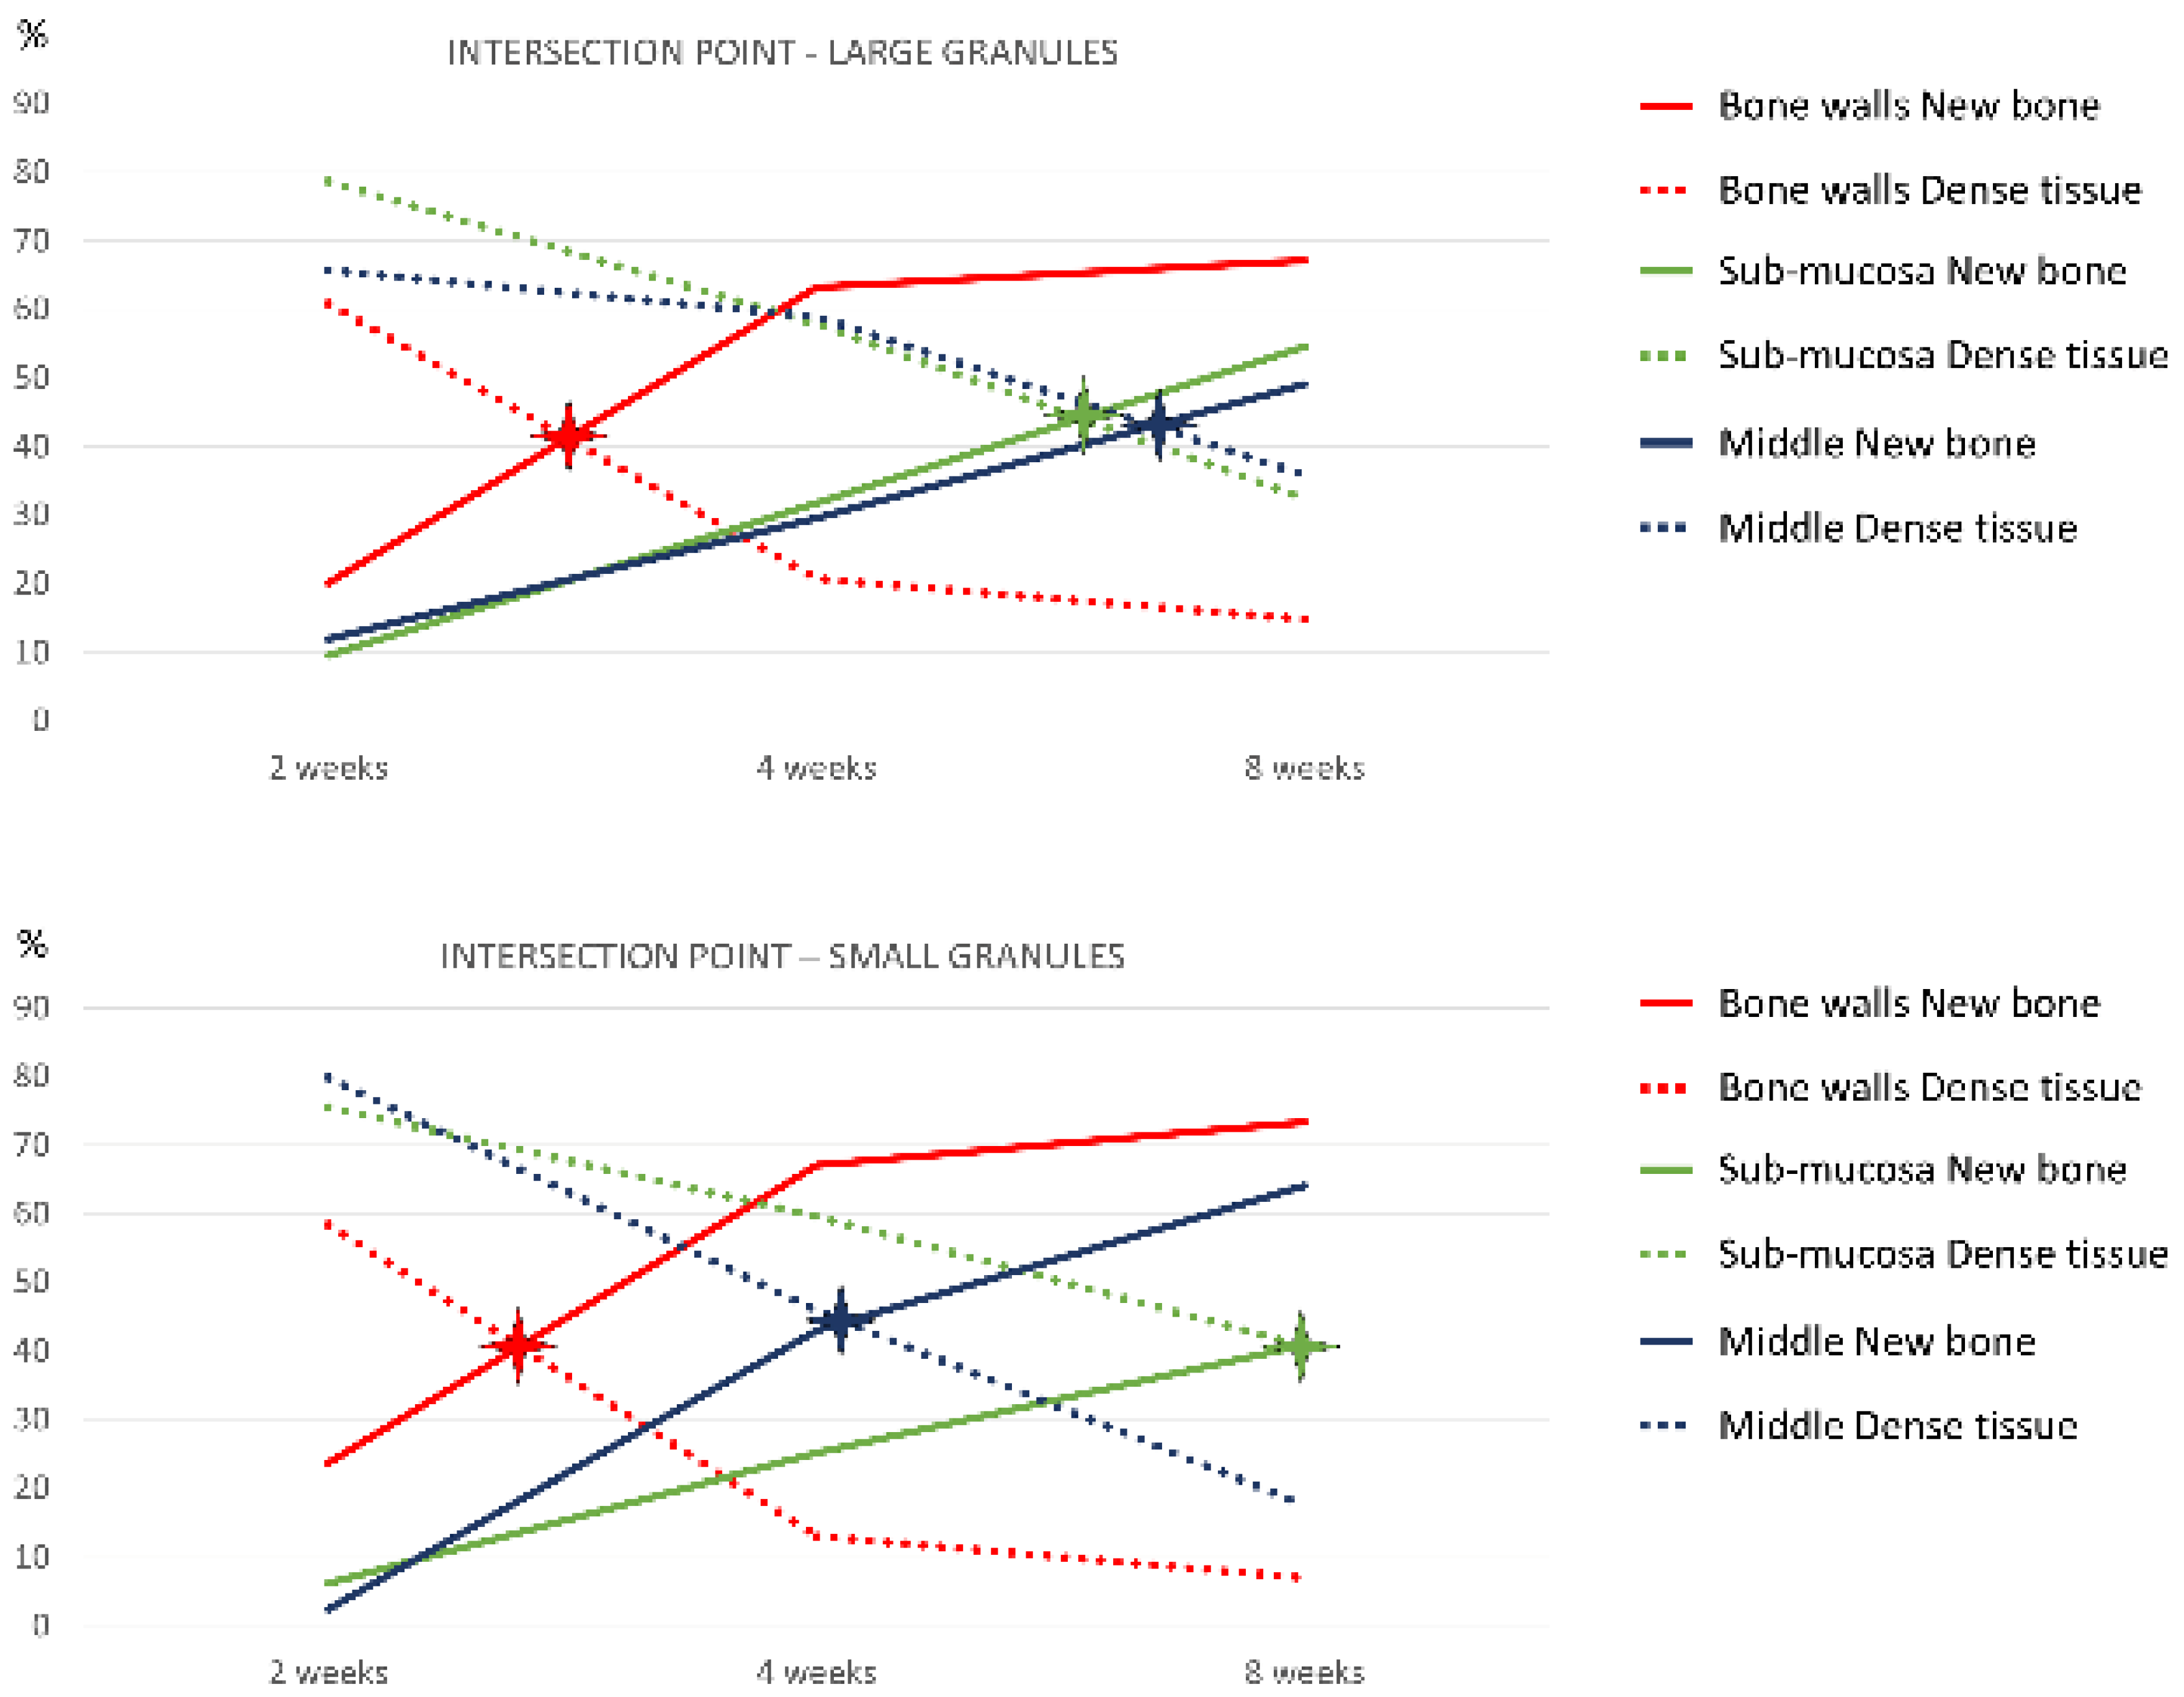

| Bone walls | 23.6 ± 14.2; 29.6 | 67.0 ± 8.2; 69.8 | 73.4 ± 6.2; 73.2 | 20.1 ± 7.7; 17.4 | 63.2 ± 19.2; 67.7 | 67.1 ± 8.1; 67.2 |

| Schneiderian | 6.2 ± 13.8; 0.0 | 25.1 ± 22.1; 25.4 | 40.8 ± 18.1; 45.0 | 9.5 ± 12.7; 4.3 | 31.7 ± 22.3; 32.9 | 54.5 ± 24.9; 57.6 |

| Middle zone | 2.4 ± 5.4; 0.0 | 42.9 ± 23.1; 39.6 | 64.0 ± 20.6; 70.0 | 11.9 ± 15.6; 4.8 | 29.6 ± 23.9; 24.1 | 49.1 ± 22.0; 53.1 |

| Close window | 3.1 ± 4.8; 0.0 | 47.2 ± 15.3; 52.8 | 74.8 ± 4.6; 76.9 | 0.0 ± 0.0; 0.0 | 52.0 ± 24.4; 60.4 | 71.9 ± 8.7; 74.5 |

| Full area | 10.9 ± 6.3; 12.5 | 48.6 ± 13.1; 46.3 | 65.0 ± 3.7; 65.9 | 11.9 ± 5.9; 11.5 | 49.1 ± 18.2; 48.3 | 62.0 ± 8.7; 61.8 |

| Bone Walls | Schneiderian | Middle Zone | Close Window | Full Area | |

|---|---|---|---|---|---|

| Small granules | 19.5; 40.6% | 55.9; 40.8% | 28.6; 44.5% | 26.1; 41.1% | 25.4; 41.6% |

| Large granules | 20.8; 41.2% | 43.2; 44.0% | 47.3; 43.0% | 24.6; 39.5% | 25.3; 42.0% |